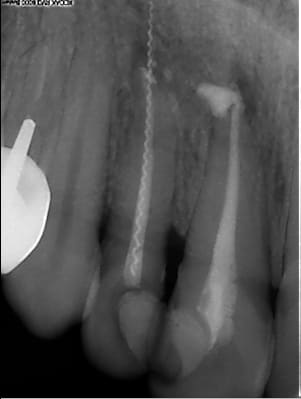

Nouveau système de transfixation par un lentulo, à breveter…

Image 1 ngh7tm - Eugenol

Pas mal du tout le lentulo! (il manque le col du lentulo qund meme.... lol)

Le lentulo, même en faisant exprès je sai pas si j'arriverai à faire mieux...;)combien d'année d'experience de TR lentulo et pâte pour arriver à ce niveau?? lol

> Nouveau système de transfixation par un lentulo, à

> breveter…

rassures moi tu la ressorti ce lentulo?

Il est sorti sans trop de problème et la patiente l'a conservé pour avoir une discussion avec son ancien CD…